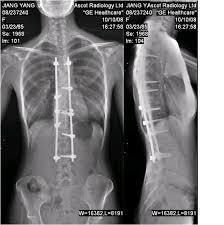

先说X射线,就是著名的伦琴发明的,影响医学的开端。X线发明的故事大家也都熟悉,伦琴在一个偶然的机会下从X射线现中看见了自己手的骨骼。所以说X射线主要是用来看骨头。此外还有一个最常见的作用是拍胸片,主要是粗略的看一下肺部和心脏的轮廓。一些诸如肺部感染,先天性心脏病导致心脏的大小形态变化,还有肺癌之类的典型的影像表现还是可以一目了然。还有人问什么透视和拍片有什么区别。简单的说透视就是医生在X光下看一眼,拍片就是把片子打印出来。

下面就是CT。X线的扫描等于把人体压成一张薄薄的纸来观察,但是只有一个方向,CT就是把人切成一个个薄片,相当于多层的X线扫描。可以把人切成1cm 的薄片,也可以切成0.5cm。越薄精确度就越大。再举个简单的例子,人体的肿瘤就像在馒头里藏了一颗沙子。X线可以看穿馒头,发现沙子,但是仅仅是平面效果。也就是仅仅在一个平面上,只知道在馒头中间有沙子,并不知道在馒头里面多深的位置。这时候就需要CT,比如说0.5cm的扫描,就相当于把馒头间隔0.5cm切片,把每一片拿出来找这颗沙子。这时候,稍微大点的沙子都可以被发现。而且可以确定在多深的位置。但是如果是更小的沙子就,刚好在0.5cm的两层之间,也可能不会被发现。